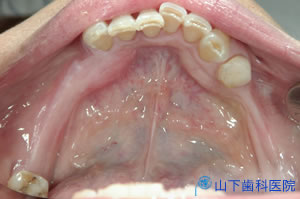

| 初診時上顎咬合面観 | ![]() |

| 初診時下顎咬合面観 治療は下顎から開始しました。銀歯を外し、根の治療状態に不安があれば再治療しました。 歯髄を失った根の治療は、最善を尽くしても、もともとの歯髄の再生、つまりは血の巡りを再建できないので治らないとお話しました。歯髄が生きている歯でないと長く持つ保証はできません。 血の巡りを失わらせた場での弱毒型常在菌バイオフィルム感染症は場ごと取り去らないかぎり治癒しない、免疫的排除が働かないために完治しない、この点では強毒型ウイルス感染症が激しい全身症状を引き起こして死亡することもあるが、治れば完治して免疫記憶に刻まれるのとは違う厄介さがあります。 根の中への再感染を防ぎ、歯髄を失ったために弱体化する歯質を補強するためには、接着歯学に基づいた土台建て(接着支台築造)を行うことが、現実にできる最善の策です。すべての土台をこの方法で建て直しました。 下顎の左右臼歯部の理想的な咬み合せ面を作るべく、割れないセラミックと言われているイットリウム安定化酸化ジルコニウムを素材にしたブリッジ、単独冠(クラウン)修復をドイツ人技工士が開発したZirkonzahn社のシステムの改良版で行いました。 |

![]() |